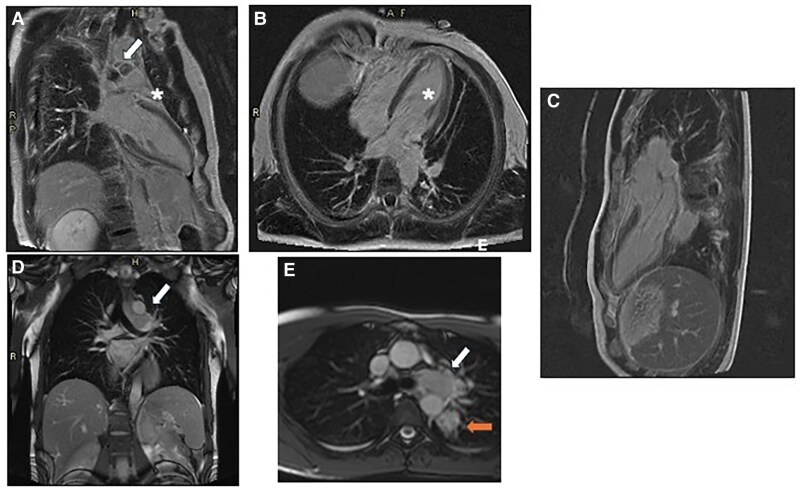

Case summary: We herein report the case of a 33-year-old male patient who presented to the Emergency Department with fever and chest pain after returning from a journey from a tropical region in Centre America. Initial tests showed elevated high-sensitivity troponin T (Hs-TnT) levels, suggesting possible cardiac involvement, but EKG and chest X-ray were normal. Echocardiography detected hypokinesis of the interventricular septum and a small pericardial effusion. Cardiac magnetic resonance (CMR) showed left ventricular function at lower normal limits and a small pericardial effusion, but also masses in the lungs and mediastinum, confirmed by computed tomography. Biopsy was performed, and histology revealed disseminated histoplasmosis. The patient was treated with antifungals and was discharged after two weeks, continuing antifungal administration in the outpatient clinic for 18 months. Follow-up imaging showed significant reduction of the masses. The patient remained asymptomatic with no further treatment needed.

Discussion: In this case report, we emphasize the essential role of a multimodal imaging approach in diagnosing cardiac inflammatory diseases. CMR was pivotal providing a three-dimensional perspective of the mediastinum, which led to the identification of a retrocardiac mediastinal mass that might have otherwise gone undetected. This highlights the importance of integrating multimodality imaging techniques to improve diagnostic accuracy and guide effective treatment strategies.